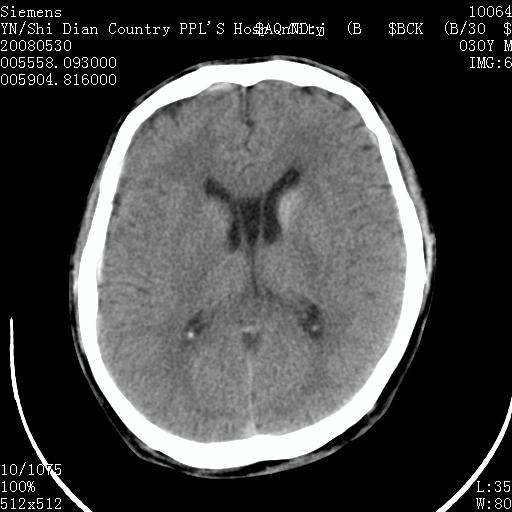

以下是引用随光逐影在2008-7-10 15:19:00的发言:[br]1)考虑左侧尾状核钙化。2)透间隔间腔与vergae腔并存。

以下是引用卜一在2008-7-10 16:43:00的发言:[br]1)考虑左侧尾状核钙化。2)透间隔间腔形成。支持!